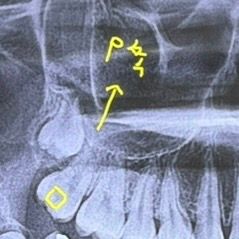

치아 p축이 뭔가요.. 설명들었는데 기억이 안나요..ㅜㅜㅜ

P축이 먼가요.. 그냥 세로로 충치 있다는건가요?

검색해도 안나와서 여기 물어봅니다… 설명해주시면 감사할 것 같습니다!!!

상악에 있는 치아에서 p라는 단어가 쓰였다면 구개부 palatal 입천장 부위라는 의미일 가능성이 높습니다.

치과에서 흔히 위치아 p면이라고 하면 palatal 즉 입천장쪽을 말합니다 buccal 볼쪽 - palatal 입천장쪽 이렇게 대비되는 용어입니다

사진에 적힌 건 충치가 있는 방향 설명하면서 p쪽 이라고 적은거 같습니다

치아에서 p라는 단어는 palatal 구개측 측 입천장 쪽을 말한다고 생각하시면될것같습니다.